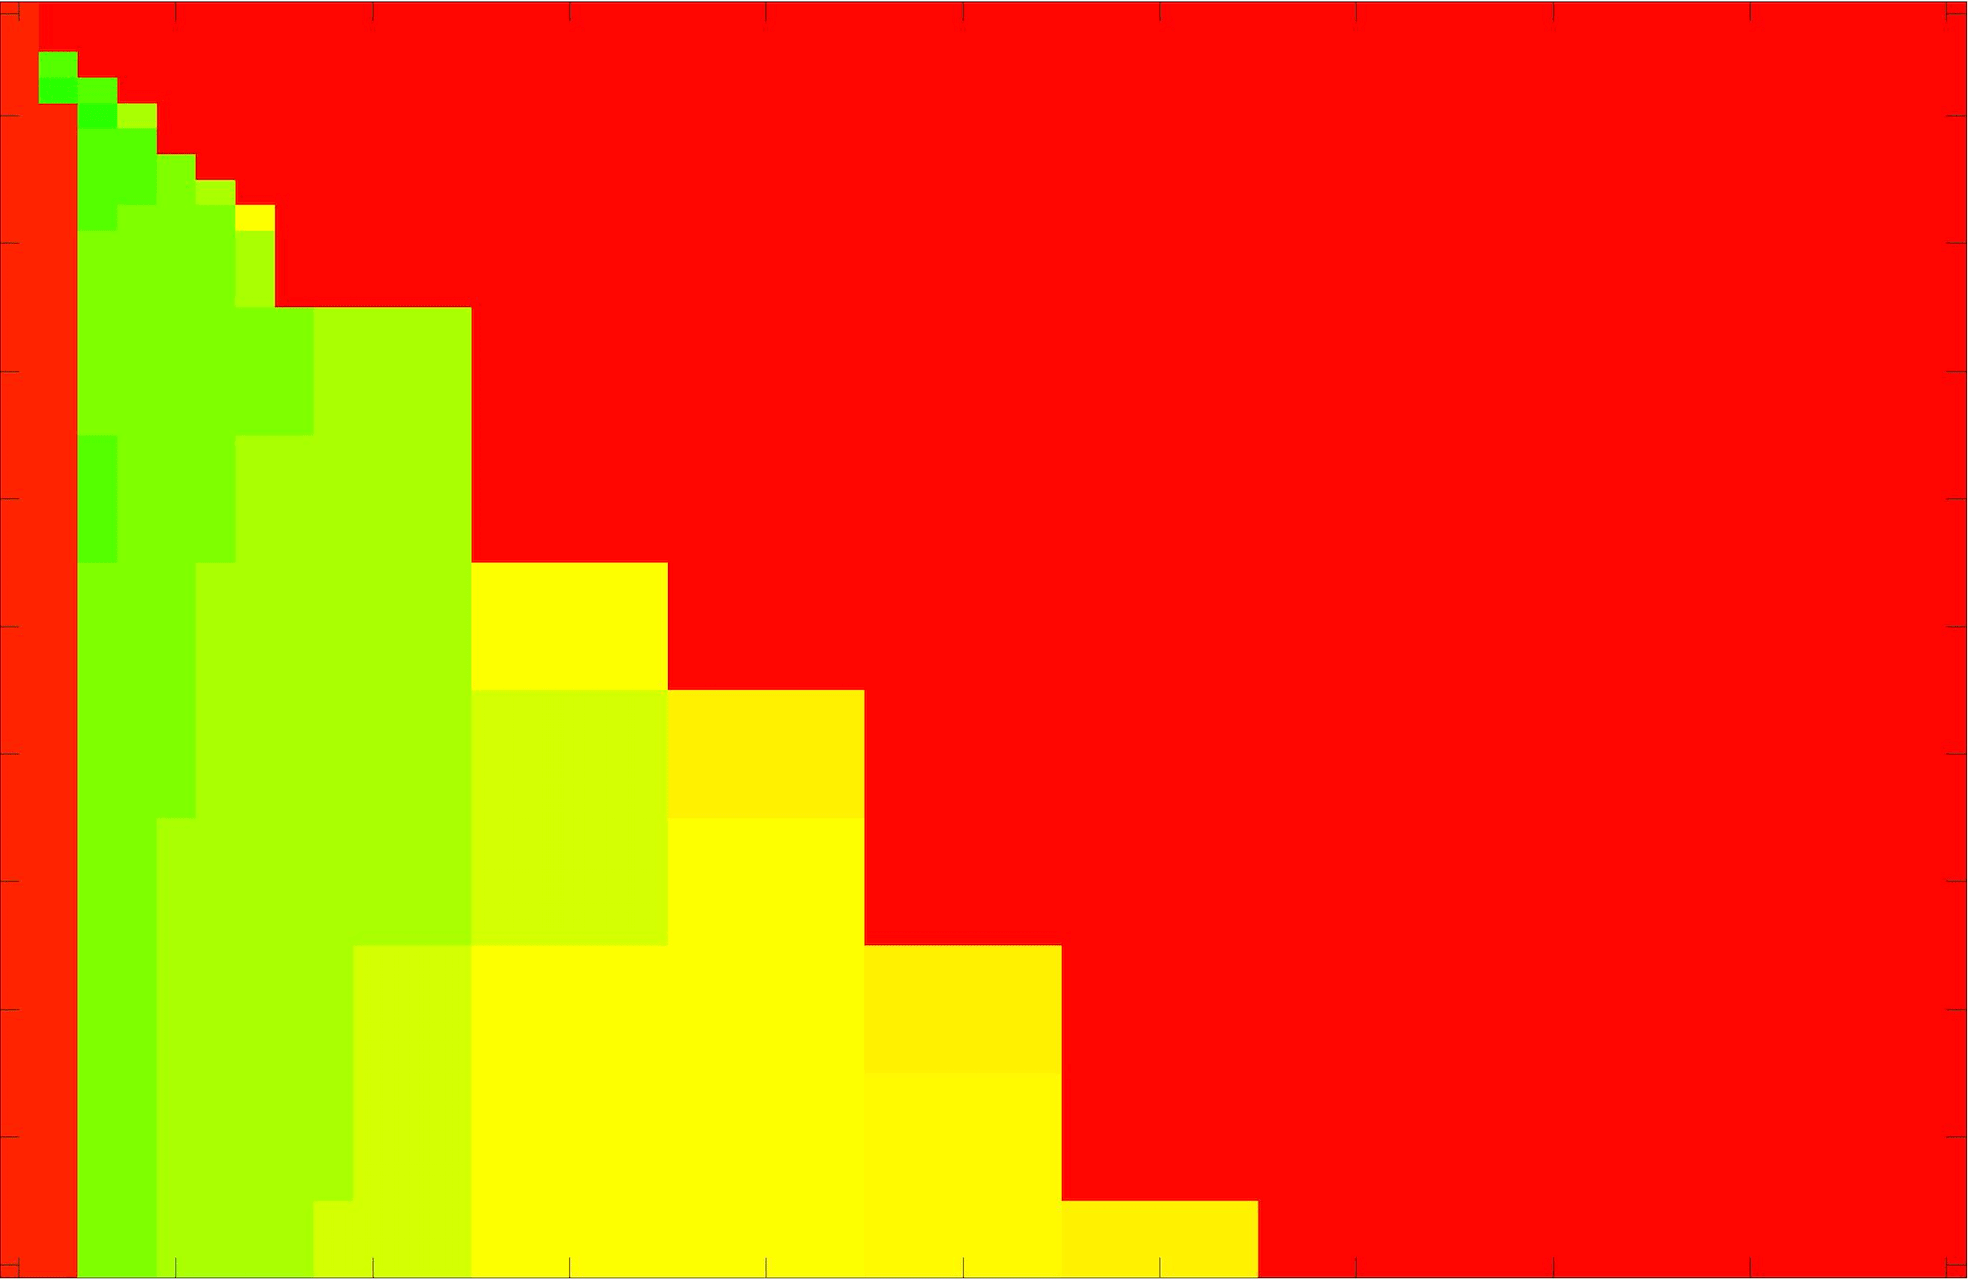

where refers to the number of points in the enclosed region. This takes values in the range , with higher TC values indicating a more accurate segmentation. In the following we will represent accuracy visually from red () to green (), with the intermediate scaling of colours used shown in Fig. 8. This will be particularly relevant in §7.2.

The TC values for the parameter sets are presented as heatmaps in Figs. 11–13. A heatmap is a convenient way to display accuracy results for hundreds of tests concisely. In Fig. 9 we give an example heatmap with the same axes used for those in Figs. 11–13. For each of the combinations of parameter values we give the TC value of the segmentation result and represent it by the appropriate colour. The corresponding colour scale is shown in Fig. 8. Qualitatively, the more green areas of the heatmap the more accurate the model is for a wider set of parameters. Example results for Test Image 5 when varying (with ) for the proposed model are given in Fig. 10. Here it can be seen what each accuracy result corresponds to visually.